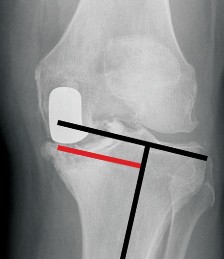

P ITFALLS Examine the preoperative lateral radiograph carefully for patella baja as these patients are poor c…